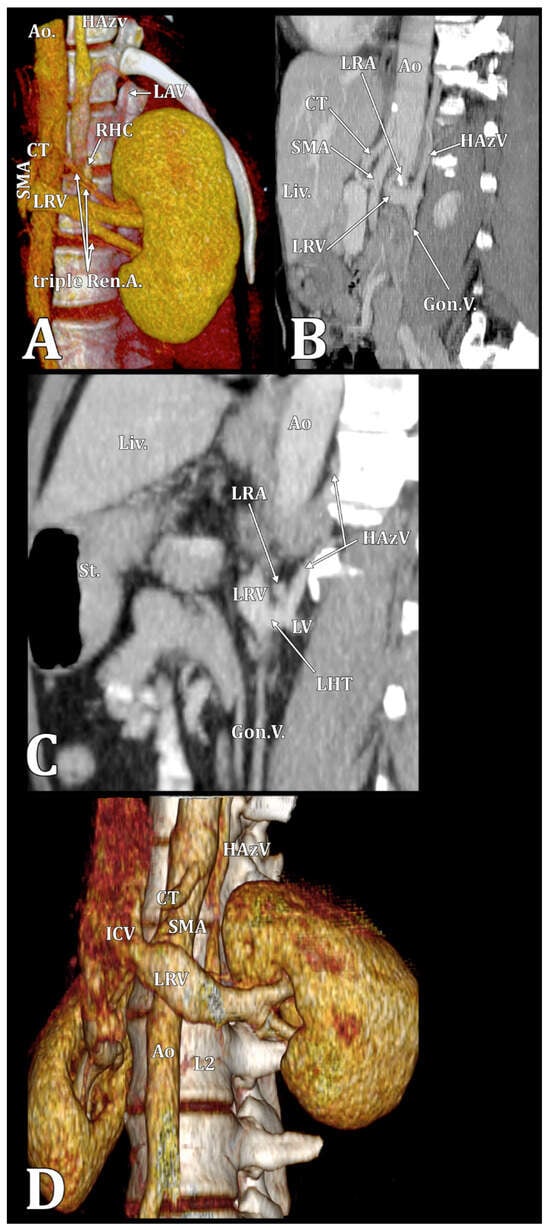

| ALV | ascending lumbar vein |

| CLRV | circumaortic left renal vein |

| CT | computed tomography |

| HAzV | hemiazygos vein |

| LRV | left renal vein |

| RHC | reno-hemiazygos connection |

| RLRV | retroaortic left renal vein |

| RP | retropelvic tributary |

| RA | renal artery |

| RV | renal vein |